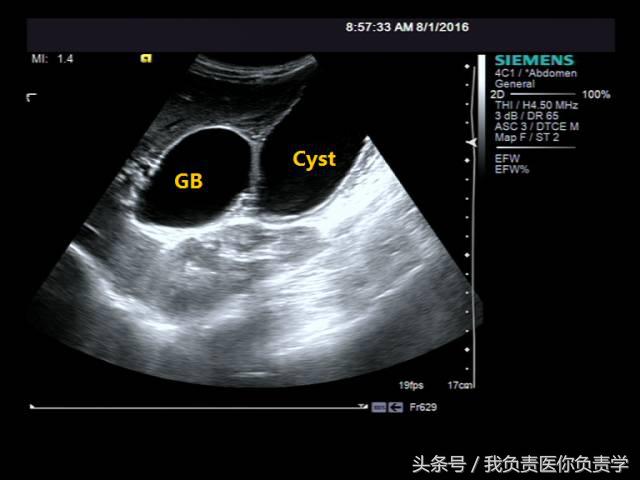

典型病例 1

患者男,64岁,因右上腹疼痛半月余就诊。查体发现右上腹部轻压痛,无发热。超声检查所见如下:

图2示于胆囊外侧可见一局限性囊性无回声区